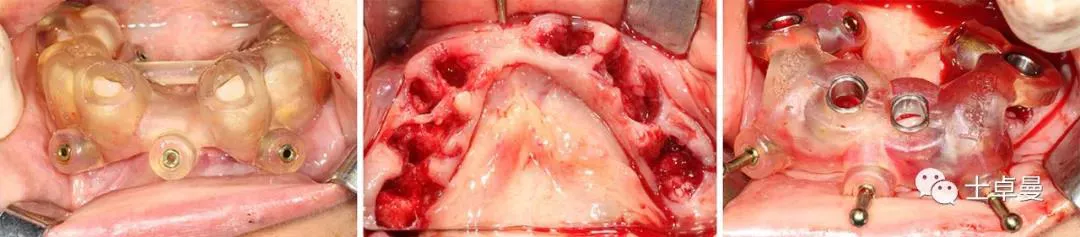

· 常规消毒碧蓝麻局麻下,利用牙支持式导板确定固位钉位置后取下导板;

· 然后分离牙龈,于牙槽嵴颊腭侧略翻瓣暴露牙根与牙槽骨间隙,切除龈瓣边缘炎性肉芽组织,拔除上颌16-27牙,球钻清理拔牙窝,并用大量生理盐水冲洗;

· 通过先前固位钉位置安放固位钉支持式种植导板,因拔牙前后软硬组织变化较大,需耐心寻找先前固位钉位置;

· 导板就位后利用Straumann BLT全程导板工具盒全程备洞,取下导板后利用测量杆确认种植体窝方向和深度以及种植窝周围骨量;

· 植入6颗Straumann BLT种植体,植入扭矩均达到45Ncm以上:

· 旋入SRA基台保护帽,修整粘膜,缝合。

下颌种植手术